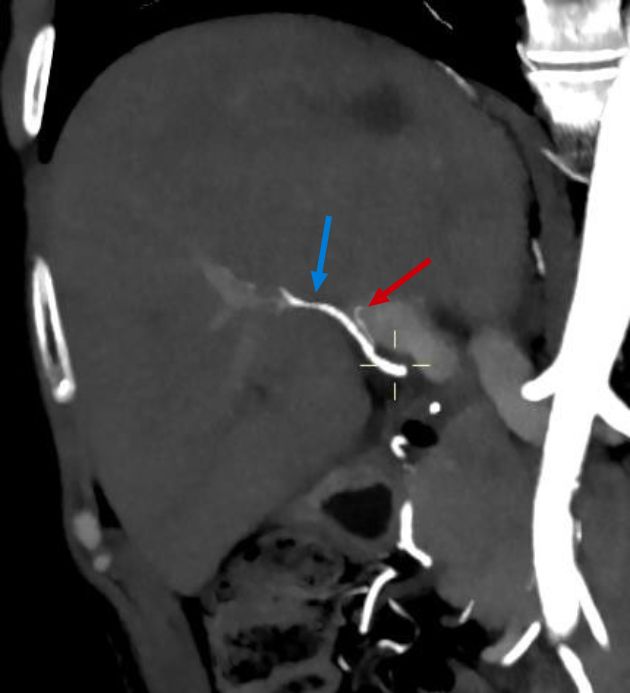

The CT angiography performed one month later showed a patent right hepatic artery and a left filiform hepatic artery (Figure 6), as well as an infarction area in segment 7/8 (Figure 7).

Patent hepatic artery of adequate caliber (blue arrow).

Figure 6. Patent hepatic artery of adequate caliber (blue arrow).

Infarction zone in segment 7/8 corresponding to the findings of the postoperative CEUS.

Figure 7. Infarction zone in segment 7/8 corresponding to the findings of the postoperative CEUS.